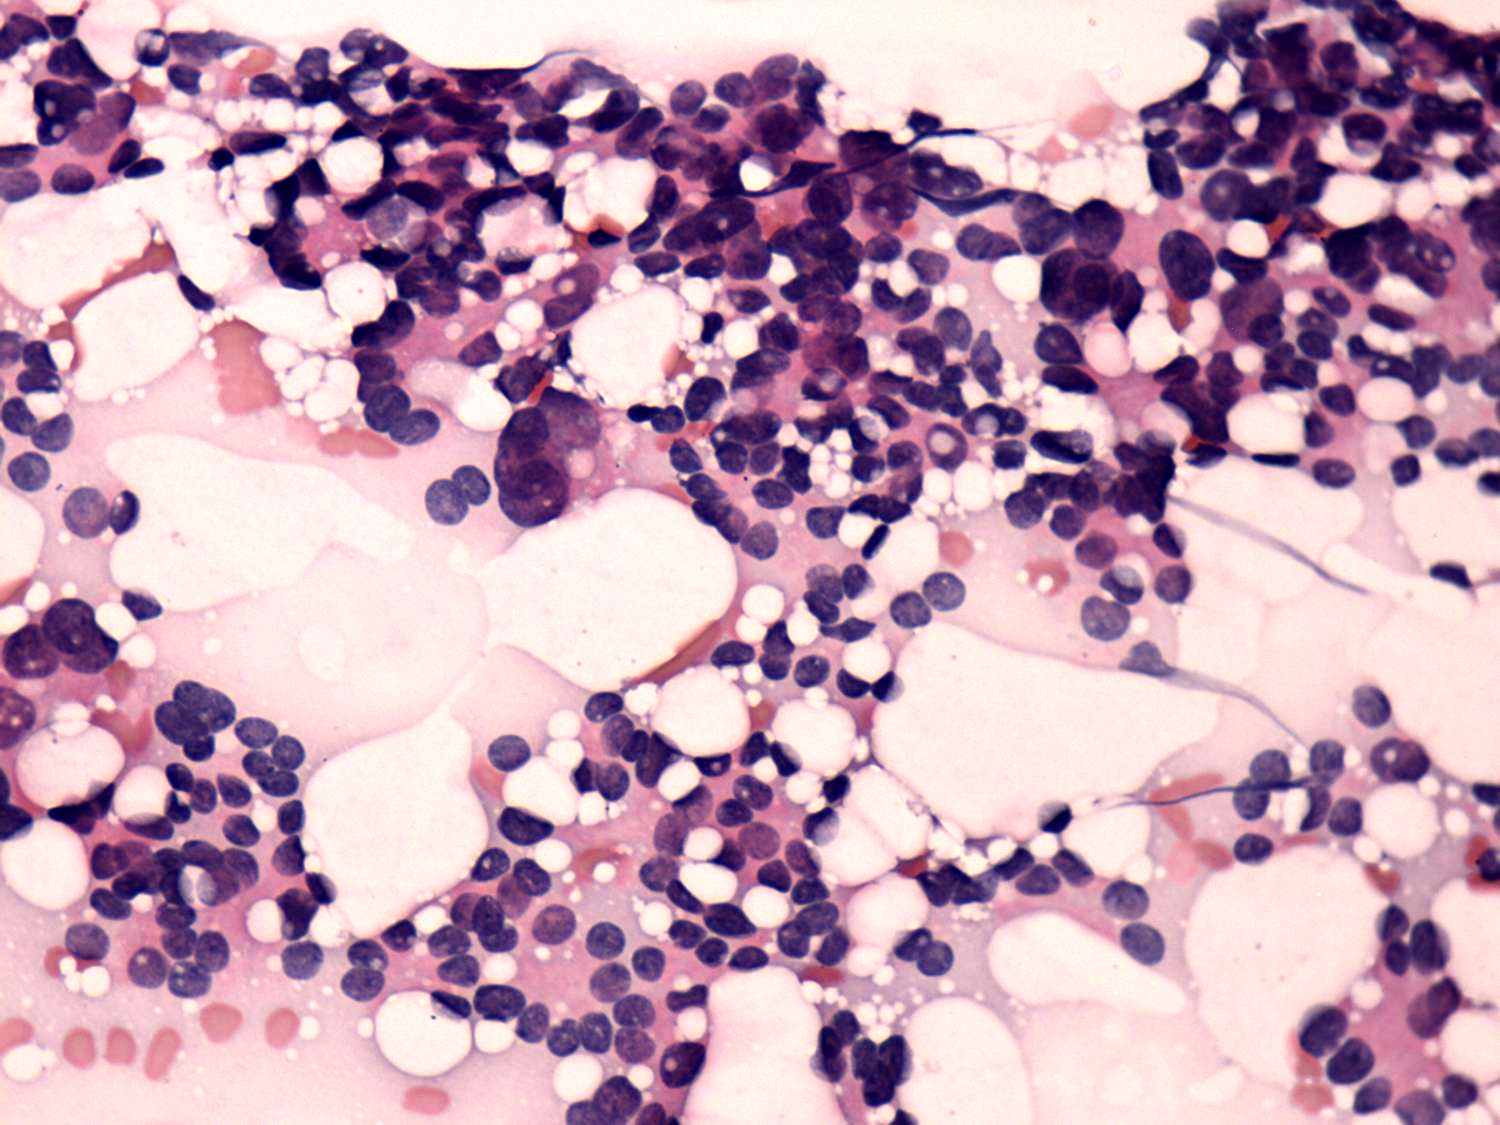

Thyroid cancers - case 665 (cytologic picture 4 of another smear)

Pap-smear, 400x. There are atypical microfollicles composed of enlarged, atypical follicular cells including several pleomorphic forms.